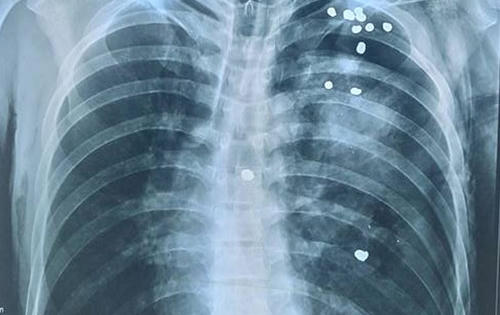

Các y, bác sĩ Bệnh viện Đa khoa tỉnh Tuyên Quang vừa tiếp nhận và cứu sống trẻ 24 tháng tuổi bị đuối nước. Đây là trường hợp cực kỳ hiếm gặp khi nạn bất tỉnh và cơ thể trước đó đã nổi trên mặt nước.